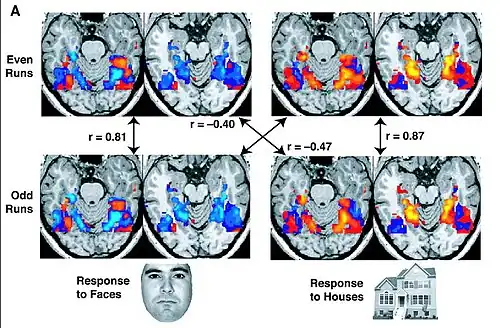

The GLM model does not take into account the contribution of relationships between multiple voxels. Whereas GLM analysis methods assess whether a voxel or region's signal amplitude is higher or lower for one condition than another, newer statistical models such as multi-voxel pattern analysis (MVPA), utilize the unique contributions of multiple voxels within a voxel-population. In a typical implementation, a classifier or more basic algorithm is trained to distinguish trials for different conditions within a subset of the data. The trained model is then tested by predicting the conditions of the remaining (independent) data. This approach is most typically achieved by training and testing on different scanner sessions or runs. If the classifier is linear, then the training model is a set of weights used to scale the value in each voxel before summing them to generate a single number that determines the condition for each testing set trial. More information on training and testing classifiers is at statistical classification.[62] MVPA allows for inferences about the information content of the underlying neural representations reflected in the BOLD signal,[63] though there is a controversy about whether information detected by this method reflects information encoded at the level of columns, or higher spatial scales.[64] Moreover, its harder to decode information from the prefrontal cortex compared to visual cortex and such differences in sensitivity across regions makes comparisons across regions problematic.[65] Another method used the same fMRI dataset for visual object recognition in the human brain is depending on multi-voxel pattern analysis (fMRI voxels) and multi-view learning which is described in,[66] this method used meta-heuristic search and mutual information to eliminate noisy voxels and select the significant BOLD signals.